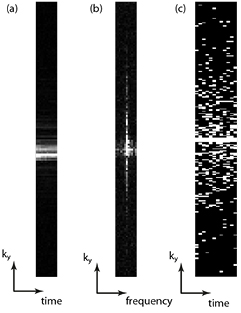

3.5. Spatiotemporal sparsity

So far the discussion has concentrated on sparsity within static images. Clearly those image modalities where repeated images are taken with common image information, such as following the uptake in a DCE-MRI experiment using T1-w imaging, or measuring cardiac function by cine acquisition throughout the heartbeat, may have the potential for sparsity between the dynamics of the study. This means that additional constraints can be added to exploit this sparsity and that sparse sampling schemes can be spatiotemporal. If we take a slice of cardiac k-space data such that we see the ky phase encode versus time, then applying a Fourier transform in both the spatial and temporal dimension gives us a compact representation in an image–frequency (usually called y–f ) space (figure 8). If we then use a spatiotemporal sparse sampling pattern, which amounts to sampling different lines of ky in different temporal phases, then we can arrange to produce non-aliased artefact in the y–f space on which a sparsity constraint (such as minimization of the L1-norm) can be imposed to recover an artefact-free image. Examples of algorithms exploiting spatiotemporal sparsity include k–t FOCUSS (Jung et al 2007) and k–t SPARSE SENSE (Otazo et al 2010). Methods exploiting properties of compressed sensing are only a small subset of the temporal acceleration techniques available (Tsao and Kozerke 2012): in particular using a temporal Fourier transform is not necessarily the sparsest representation of the time domain and principal component analysis in the temporal dimension has also been implemented (Pedersen et al 2009).

Figure 8. (a) An intensity plot of the ky dimension versus time for a cardiac cine acquisition showing the similarity of the central k-space through the cardiac cycle. (b) If the time dimension is Fourier transformed, it can be seen that the resulting ky–f space is sparse and this can be used to constrain (c) a spatiotemporal undersampling scheme, here shown a with 4× acceleration factor.

Download figure: